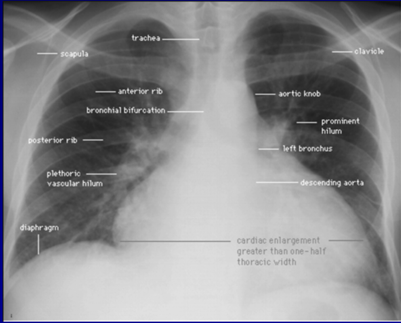

影像学表现

一大二薄三弱四返

以心房、心室增大为主,常伴有四个心腔增大扩张,且心房与心室成比例扩张。心脏重量增加,但不伴有心室壁增厚。心影明显增大、心胸比>50%、肺淤血。